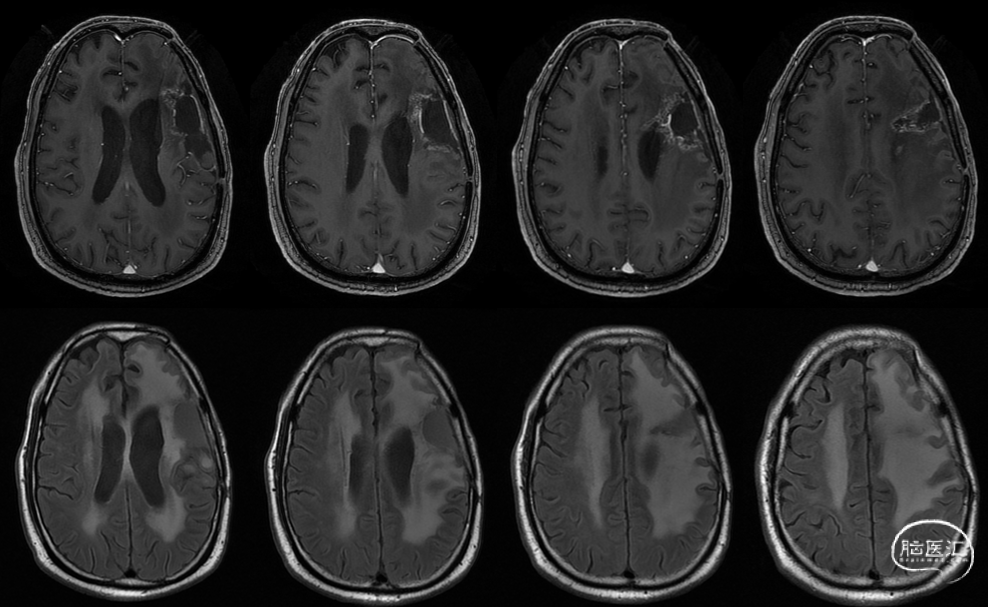

术后48小时MR,可见左额不规则混杂信号影,周围水肿:图示。

术后48小时MR,增强后边缘不规则线样强化,靠近放射冠及侧脑室壁可疑少许残存:图示。

肿瘤电场治疗16天,RT后1月(2020-07-22):图示。

放疗后8月(2021-03-17):如视频和图像。

入院前头MRI(2020-3):左侧额岛叶肿块,信号不均匀,其内可见出血和坏死,占位效应明显,周围见水肿。考虑左额岛叶肿瘤(高级别脑胶质瘤可能性大)。于2020年4月行左额岛叶占位性病变切除术。术中见肿瘤组织位于左侧额中回及额下回后部,大小约4m×5cm×5cm,呈烂鱼肉样,色灰红,质软,部分坏死,血运中等,边界不清,侵犯左侧岛叶向下挤压颞叶。显微镜下沿肿瘤周边胶质增生带完整切除肿瘤。术后48小时内复查头MRI平扫、加强,影像显示术腔边缘不规则线样强化,靠近放射冠及侧脑室壁强化明显,可疑少许残存。